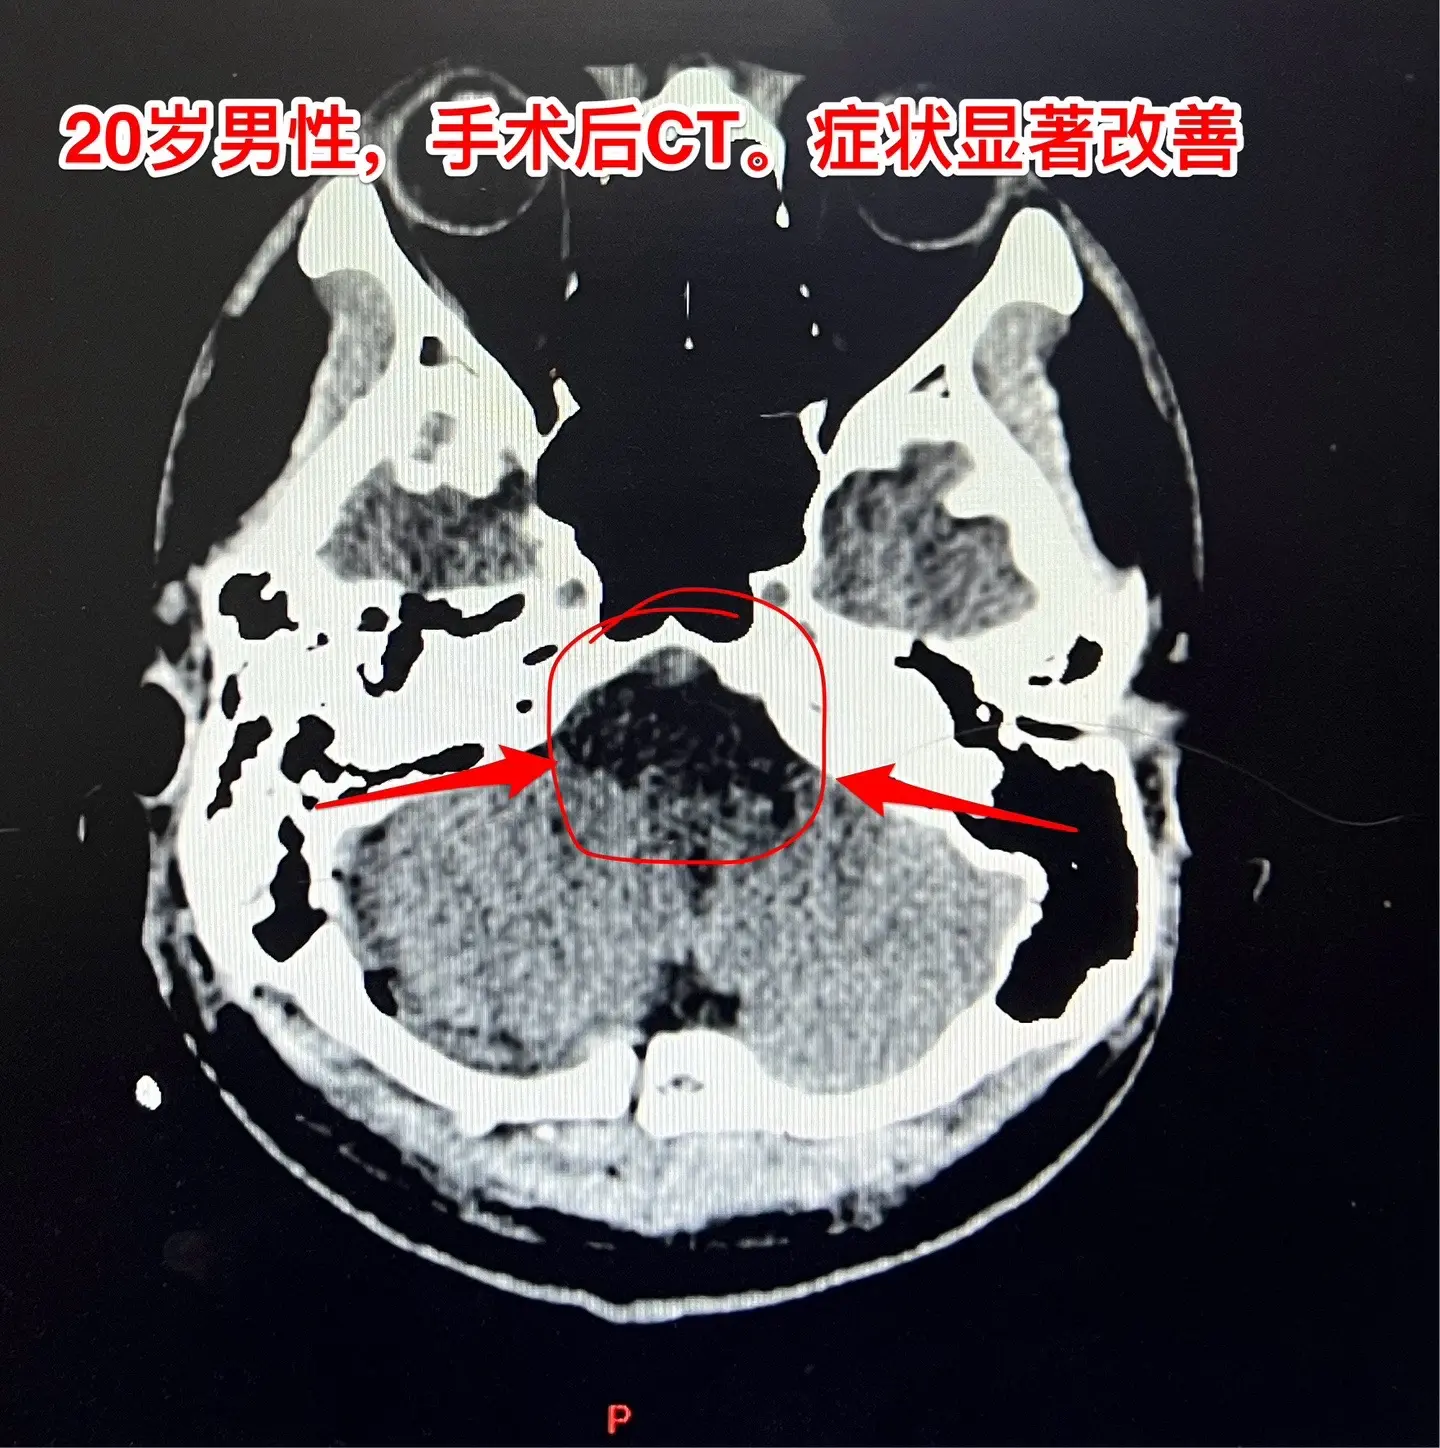

头晕、吞咽困难、行走不稳、大小便障碍。20岁漳州的小伙子,2个月前出现头晕,一个月前出现吞咽困难,半个月个月前出现多睡,一周前出现行走不稳、视物重影、发音不清晰,而且有大小便障碍。 一般人认为这些症状都是七八十岁的老人才会有的,怎么会出现在20岁的年轻人身上呢?他到底得了什么病? 磁共振和CT显示脑干腹侧有一个巨大囊肿,对脑干有明显的压迫,考虑为肠源性囊肿。针对这个病,只有选择作手术切除囊肿,病人的症状才有希望好转。 2024.8.14作了手术,术中看见囊壁与脑干的神经、基底动脉的分支血管粘连。切除大部分囊壁,清除了囊内容物,脑干得到充分减压。 手术后病人的症状显著改善了!